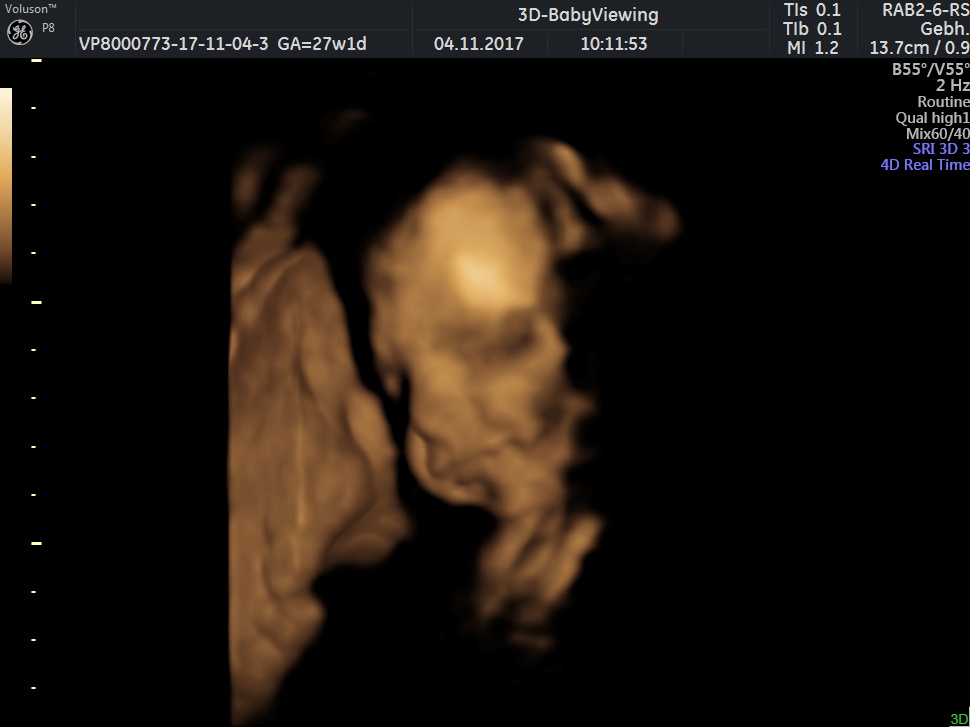

Wir waren heute beim 3D Utraschall 😍

So wir sind jetzt in der 27 SSW und sie bewegt sich sehr viel . Am Samstag fahren wir zum 3D Utraschall mal sehen ob sie kooperativ ist 😛